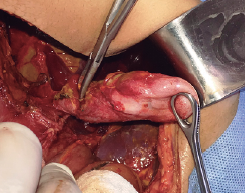

PERFORACION TRAUMATICA AISLADA DE LA VESICULA BILIAR: REVISION DE LA LITERATURA ACTUAL Y REPORTE DE UN CASO

Introducción: La lesión de la vesícula biliar secundaria a trauma abdominal cerrado constituye un evento infrecuente de perforación traumática de ella, de presentación tardía; revisamos la literatura científica actualmente disponible y además describimos un caso. Materiales y Método: Utilizando la plataforma PubMed se buscan las siguientes palabras clave: “Blunt abdominal trauma”. Se seleccionan las series con lesiones de la vesícula biliar: “Traumatic gallbladder rupture”. Se seleccionan los reportes de lesiones aisladas de la vesícula biliar: “Isolated gallbladder rupture”. Se seleccionan los reportes de presentación tardía de lesiones aisladas de la vesícula biliar: “Delayed presentation of isolated gallbladder rupture”. Resultados: De todas estas publicaciones se seleccionan las que a criterio de los autores son relevantes para el presente caso. Discusión: La mayoría de las perforaciones de la vesícula biliar se producen en vesículas sanas de paredes delgadas distendidas por el ayuno o el consumo de alcohol. No existe una presentación clínica clásica. Los estudios imagenológicos son inespecíficos y se llega al diagnóstico definitivo durante la exploración quirúrgica. El tratamiento de esta lesión es la colecistectomía. Conclusión: El diagnóstico no es fácil pero la resolución es relativamente simple y el pronóstico es bueno. El presente caso ilustra este tipo de lesiones en pacientes con trauma abdominal cerrado